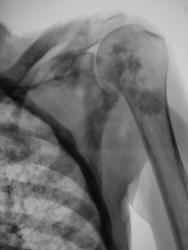

Метастаз в головку и шейку бедренной кости.

Наблюдения Виктора Григоревича.

Вот еще метастазы в кости, вот только точно не помню откуда.

Наблюдение Виталия Валерьевича.